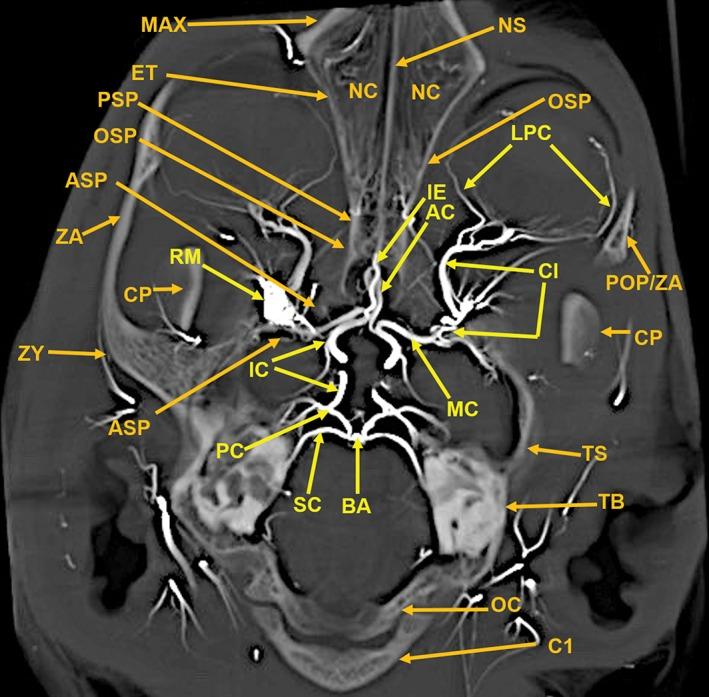

The objective of this study was to investigate the possibility of obtaining high-resolution multiplanar computed tomography (CT) imaging of the cranial arterial circulation of the cat (Felis catus), the rete mirabile, and components of the skull, utilizing preserved cat specimens with an arterial system that was injected with a radiopaque contrast compound in the early 1970s. Review of the literature shows no high-resolution CT studies of the cat's cranial circulation, with only few plain radiographic studies, all with limited cranial vascular visualization. In view of the inability of the radiographic techniques available from 1970s to mid-2000s to provide high-resolution imaging of the arterial circulation within the intact skull and brain of the cat, without dissection and histologic sectioning and disruption of tissues, no further imaging was performed for many years. In 2010, a high-resolution micro CT scanner became available, large enough to scan the entire nondissected head of the arterially injected cats. All the obtained CT images were processed with a software program that provided 3D volume rendering and multiplanar reconstruction with the ability to change the plane angulation and slab thickness. These technical features permitted more precise identification of specific arterial and bony anatomy. The obtained images demonstrated, with a nondestructive method, high-resolution vascular anatomy of the cerebral, orbital, facial arterial system, the rete mirabile, and skull bone components of the cat, with details not previously described in the literature. Anat Rec, 302:1958-1967, 2019. © 2019 The Authors. The Anatomical Record published by Wiley Periodicals, Inc. on behalf of American Association of Anatomists.

本研究旨在探讨利用上世纪 70 年代早期向动脉系统内注入造影剂的保存猫标本,获取猫颅动脉循环、网状血管和颅骨成分的高分辨率多平面计算机断层扫描(CT)成像的可能性。文献回顾表明,目前尚无关于猫颅循环的高分辨率 CT 研究,仅有少数平片研究,但都仅能有限地显示颅血管。鉴于上世纪 70 年代至 2000 年代中期的放射技术无法在不进行解剖和组织学切片及破坏的情况下,提供猫完整颅骨和大脑内动脉循环的高分辨率成像,因此多年来没有进一步进行影像学检查。2010 年,一种高分辨率的微 CT 扫描仪问世,其体积足够大,可以扫描整个经动脉注射的猫的未解剖头部。所有获得的 CT 图像都使用软件进行处理,该软件具有 3D 容积渲染和多平面重建功能,能够改变平面角度和切片厚度。这些技术特征使特定动脉和骨骼解剖结构的识别更加精确。所获得的图像以非破坏性方法显示了猫的大脑、眼部、面部动脉系统、网状血管和颅骨骨成分的高分辨率血管解剖结构,提供了文献中以前未描述过的细节。解剖学记录,302:1958-1967, 2019. © 2019 作者。解剖记录由 Wiley 期刊出版公司代表美国解剖学家协会出版。